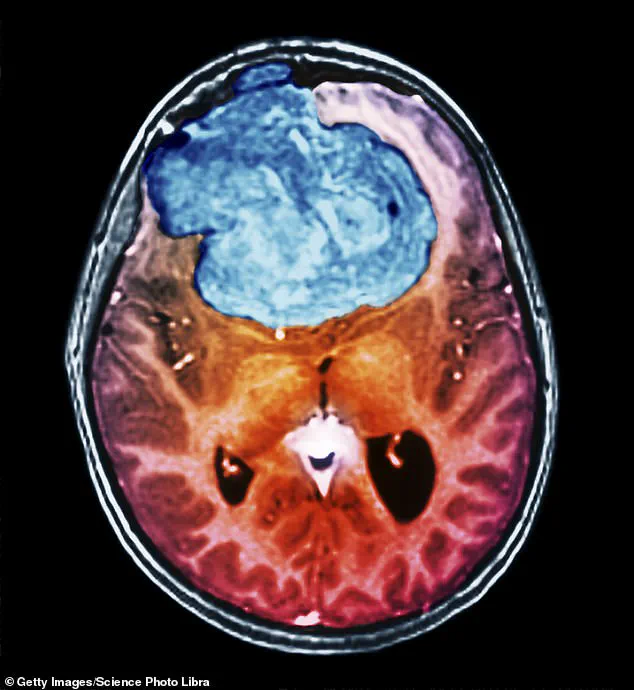

As she sat down in the eye specialist’s office, ‘I could see he had my MRI scan on his computer screen and there was a big white blob – a couple of centimetres in diameter – on the left side of my brain,’ recalls Ruth, a grandmother of three, who lives with her husband in Braintree, Essex.

It was a meningioma, a slow-growing brain tumour.

Although rarely cancerous, it can be life-threatening if it gets so big that it squashes the brain inside the skull.

The tumours are slow growing – increasing in size by about 1mm to 2mm a year – and most are only diagnosed when they are about 3cm, so they can be present for decades before causing any problems.

Meningiomas can cause vision loss, personality changes, memory loss and even paralysis.

The most common type of brain tumour – affecting 2,000 to 3,000 people a year in the UK – meningiomas form in the meninges, the outer layers of tissue that cover the brain.

They can cause vision loss, personality changes, memory loss and even paralysis.